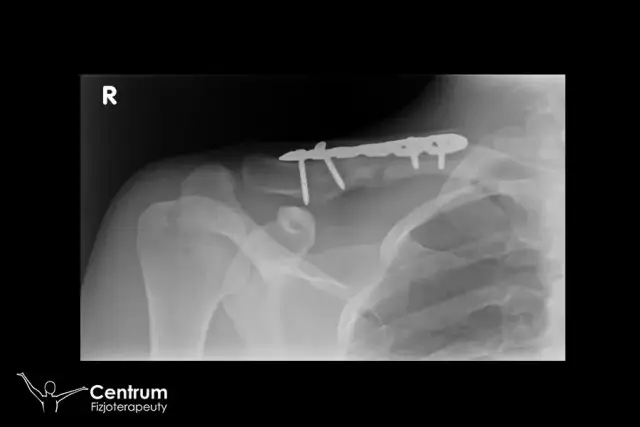

Ile trwa rehabilitacja po złamaniu obojczyka? Kluczowe informacje o czasie regeneracji

Ile trwa rehabilitacja po złamaniu obojczyka? Sprawdź, jakie czynniki wpływają na czas regeneracji i jak skutecznie wrócić do pełnej sprawności.